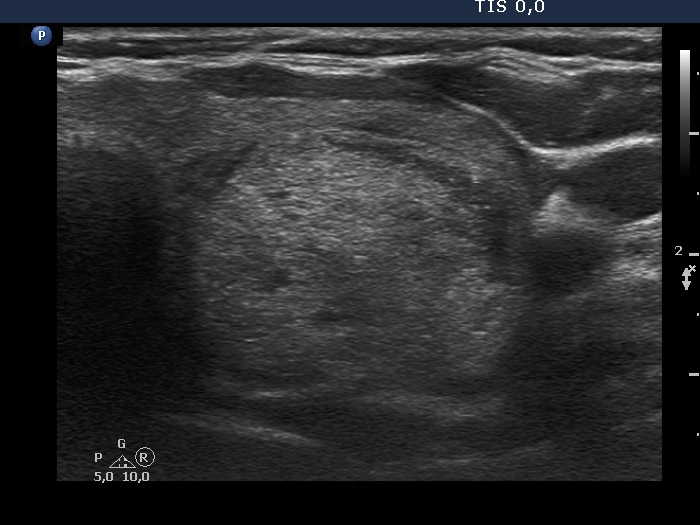

Benign hyperplastic nodules (histological diagnosis) - case 444 |

Papillary carcinoma (histological diagnosis) - case p002 |

Both lesions contain bright granules and lines, i.e. proliferation of connective tissue. The simultaneous presence of punctate echogenic foci (microcalcifications) cannot be excluded in either case. The ultrasound presentation differs in the shape and borders of the nodules. In contrast with the benign lesion, the malignant nodule is lobulated and has blurred borders in its dorsal part.